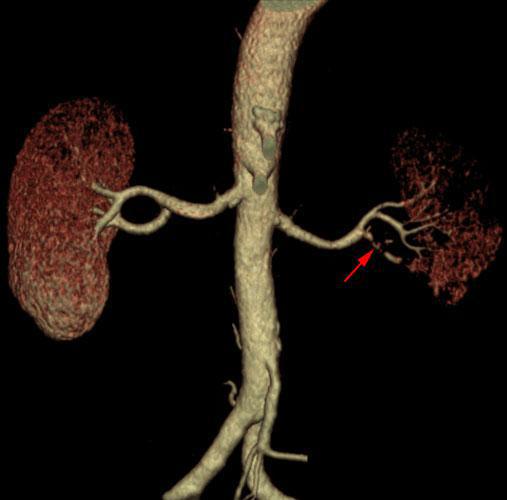

Infarto renal segmentario